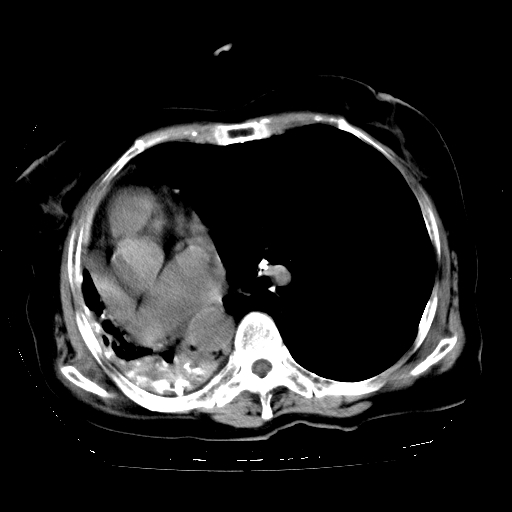

女,72岁,咳嗽、憋气一周,十年前曾患肺结核及胸膜结核。

右侧毁损肺,右侧纵隔疝

右侧毁损肺,右侧纵隔疝,左肺代偿!

1.右侧损毁肺伴胸膜钙化,2.左肺小结节灶,良性可能大,注意复查。3.肝脏左叶囊肿。4.先天性一侧肺不发育待出外(右侧胸廓无明显塌陷)。对比原片应该非常有帮助。

肝脏转移

右侧肺毁损,左肺代偿性肺气肿,纵隔疝。